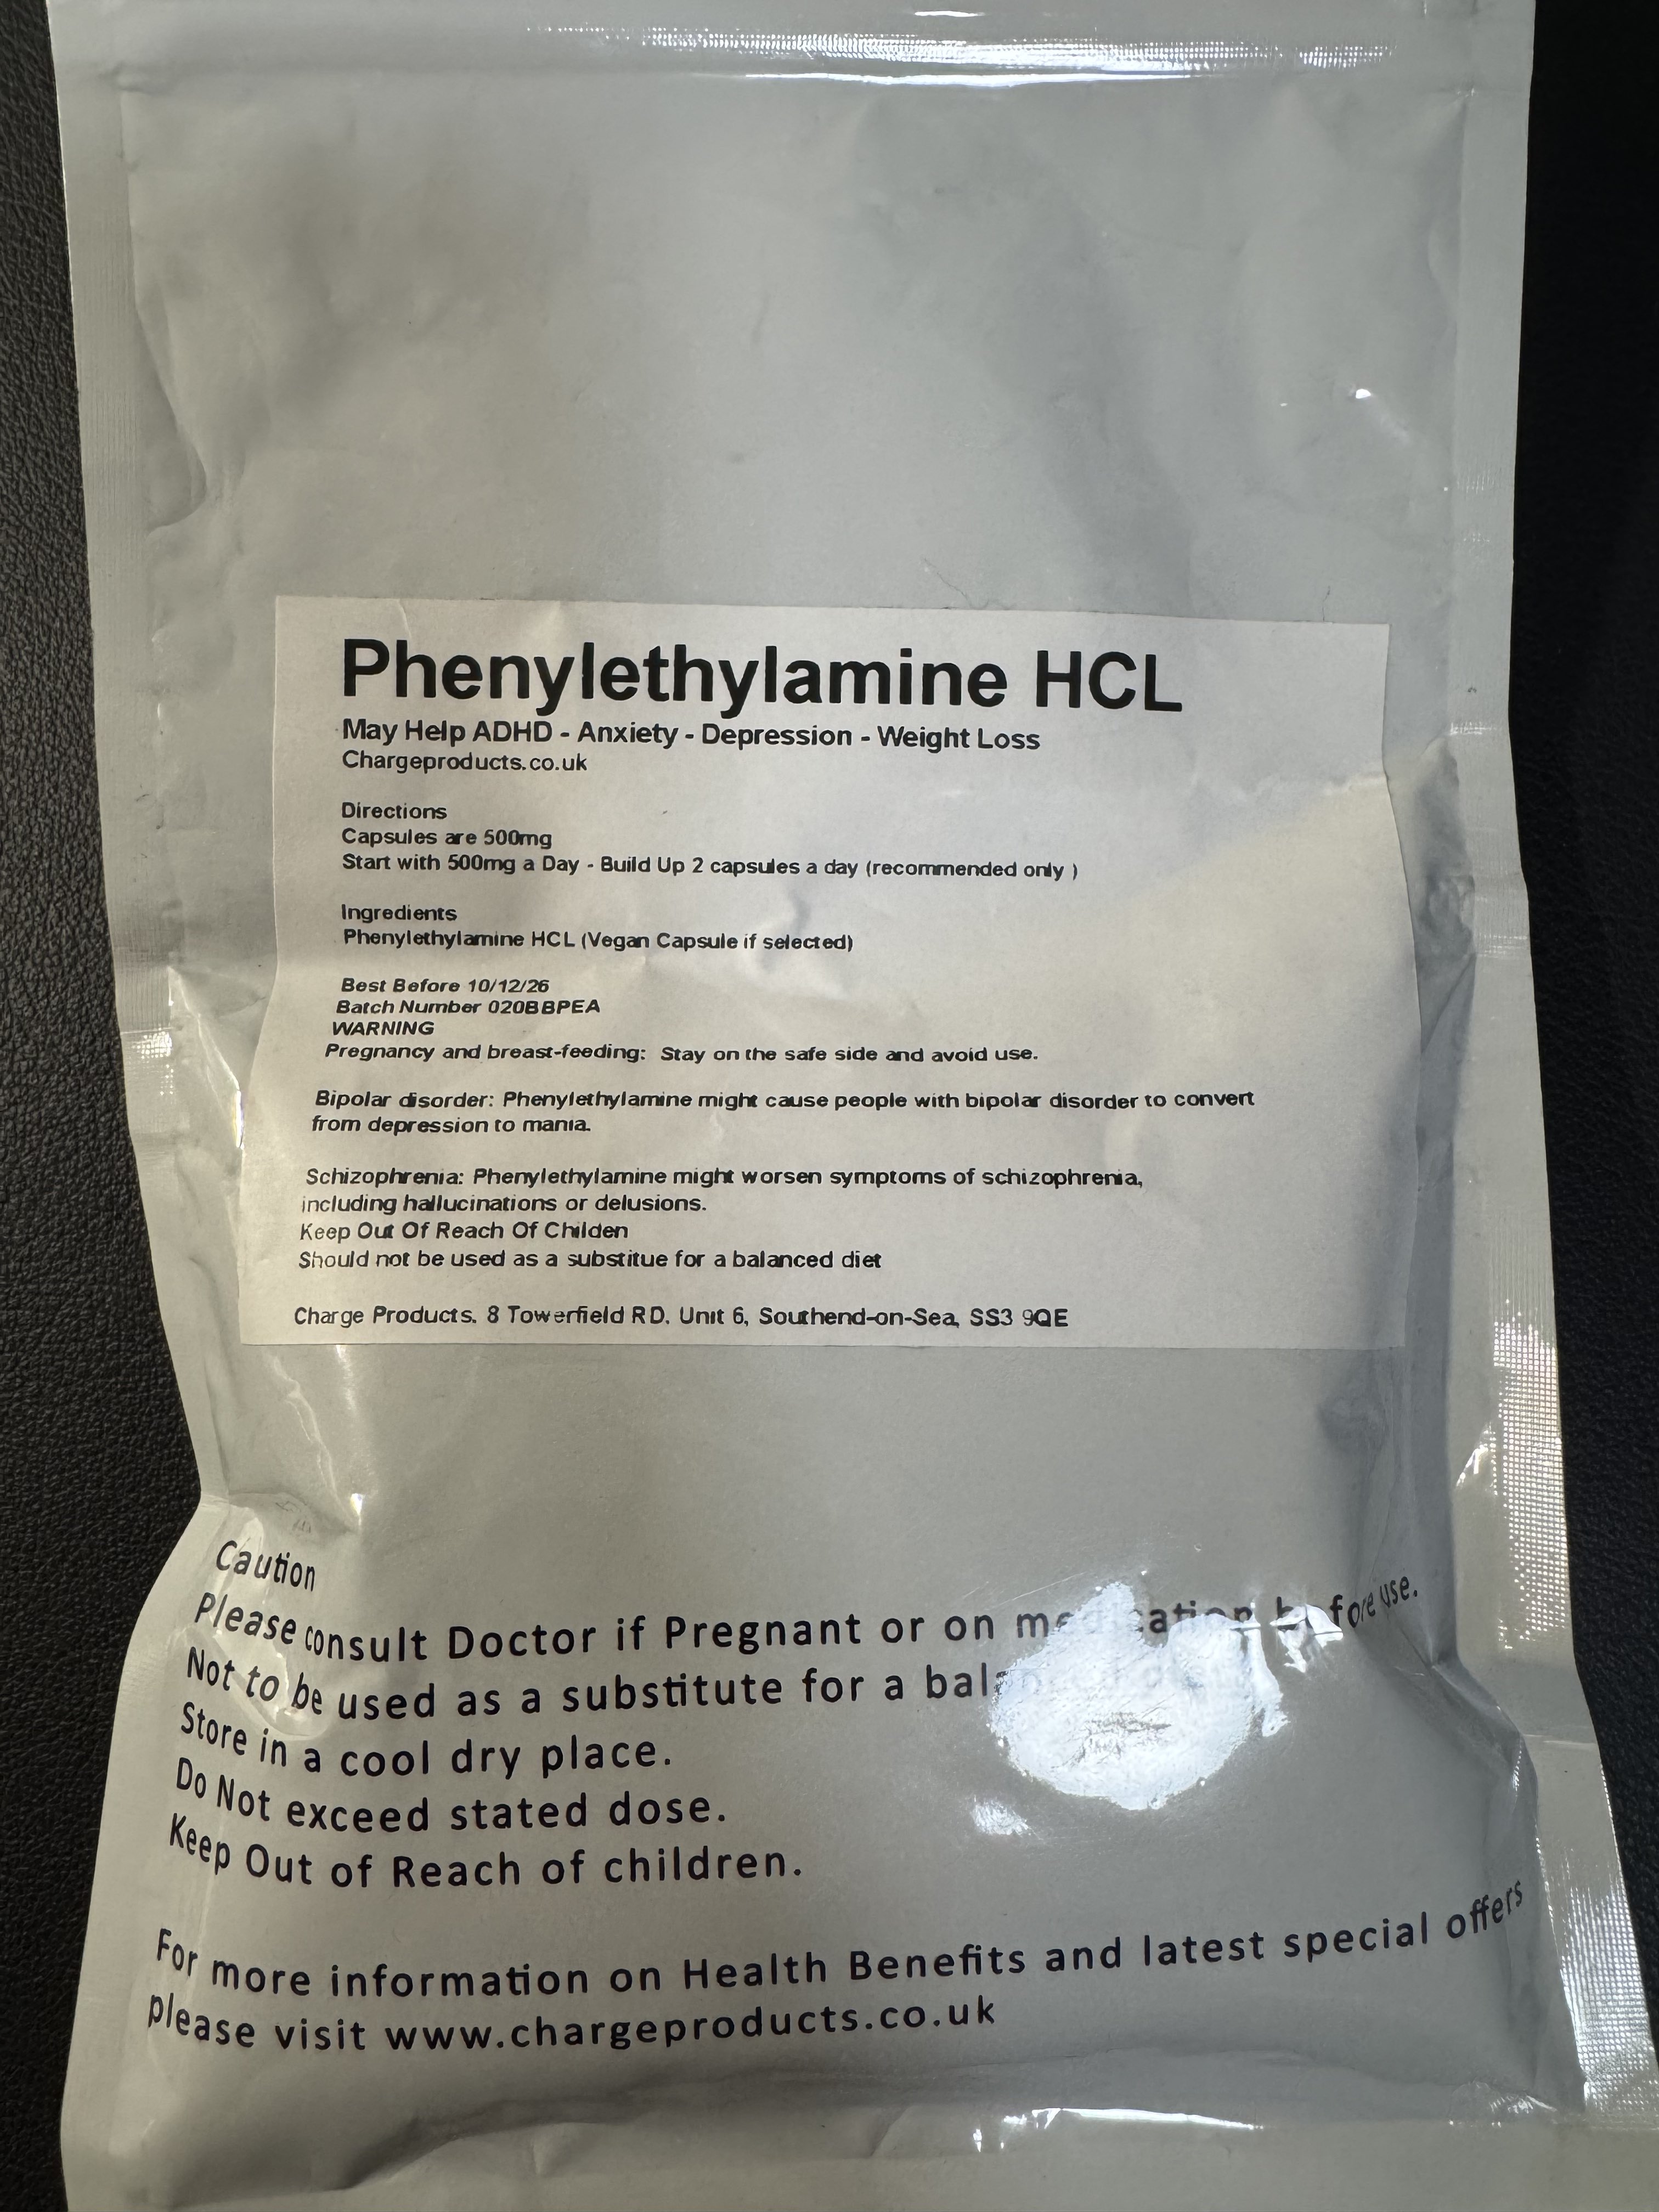

2025-03-25 05:53:33 UTC

联用时最好备上血压计和速效降压药,或者苯二氮卓,因为剂量大时可能会导致高血压和头痛

就我个人体验而言建议从300mg试起

不建议加上这两种以外的其他药物如安非他酮和TCP,会导致更严重的副作用

司来吉兰和pea都不建议鼻吸,因为司来粘膜吸收会使效果不可控,即更高的生物利用度;pea是因为很痛